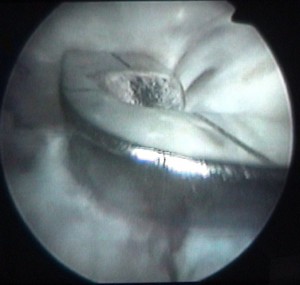

cette vis sert à attacher le ligament |

et elle est maintenant vissée à fond |